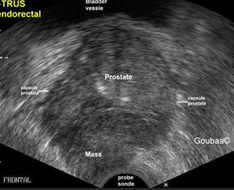

If other tests raise concerns, your doctor may use transrectal ultrasound to further evaluate your prostate. A

small probe, about the size and shape of a cigar, is inserted into your rectum. The probe uses sound waves

to make a picture of your prostate gland.To know more Click Here